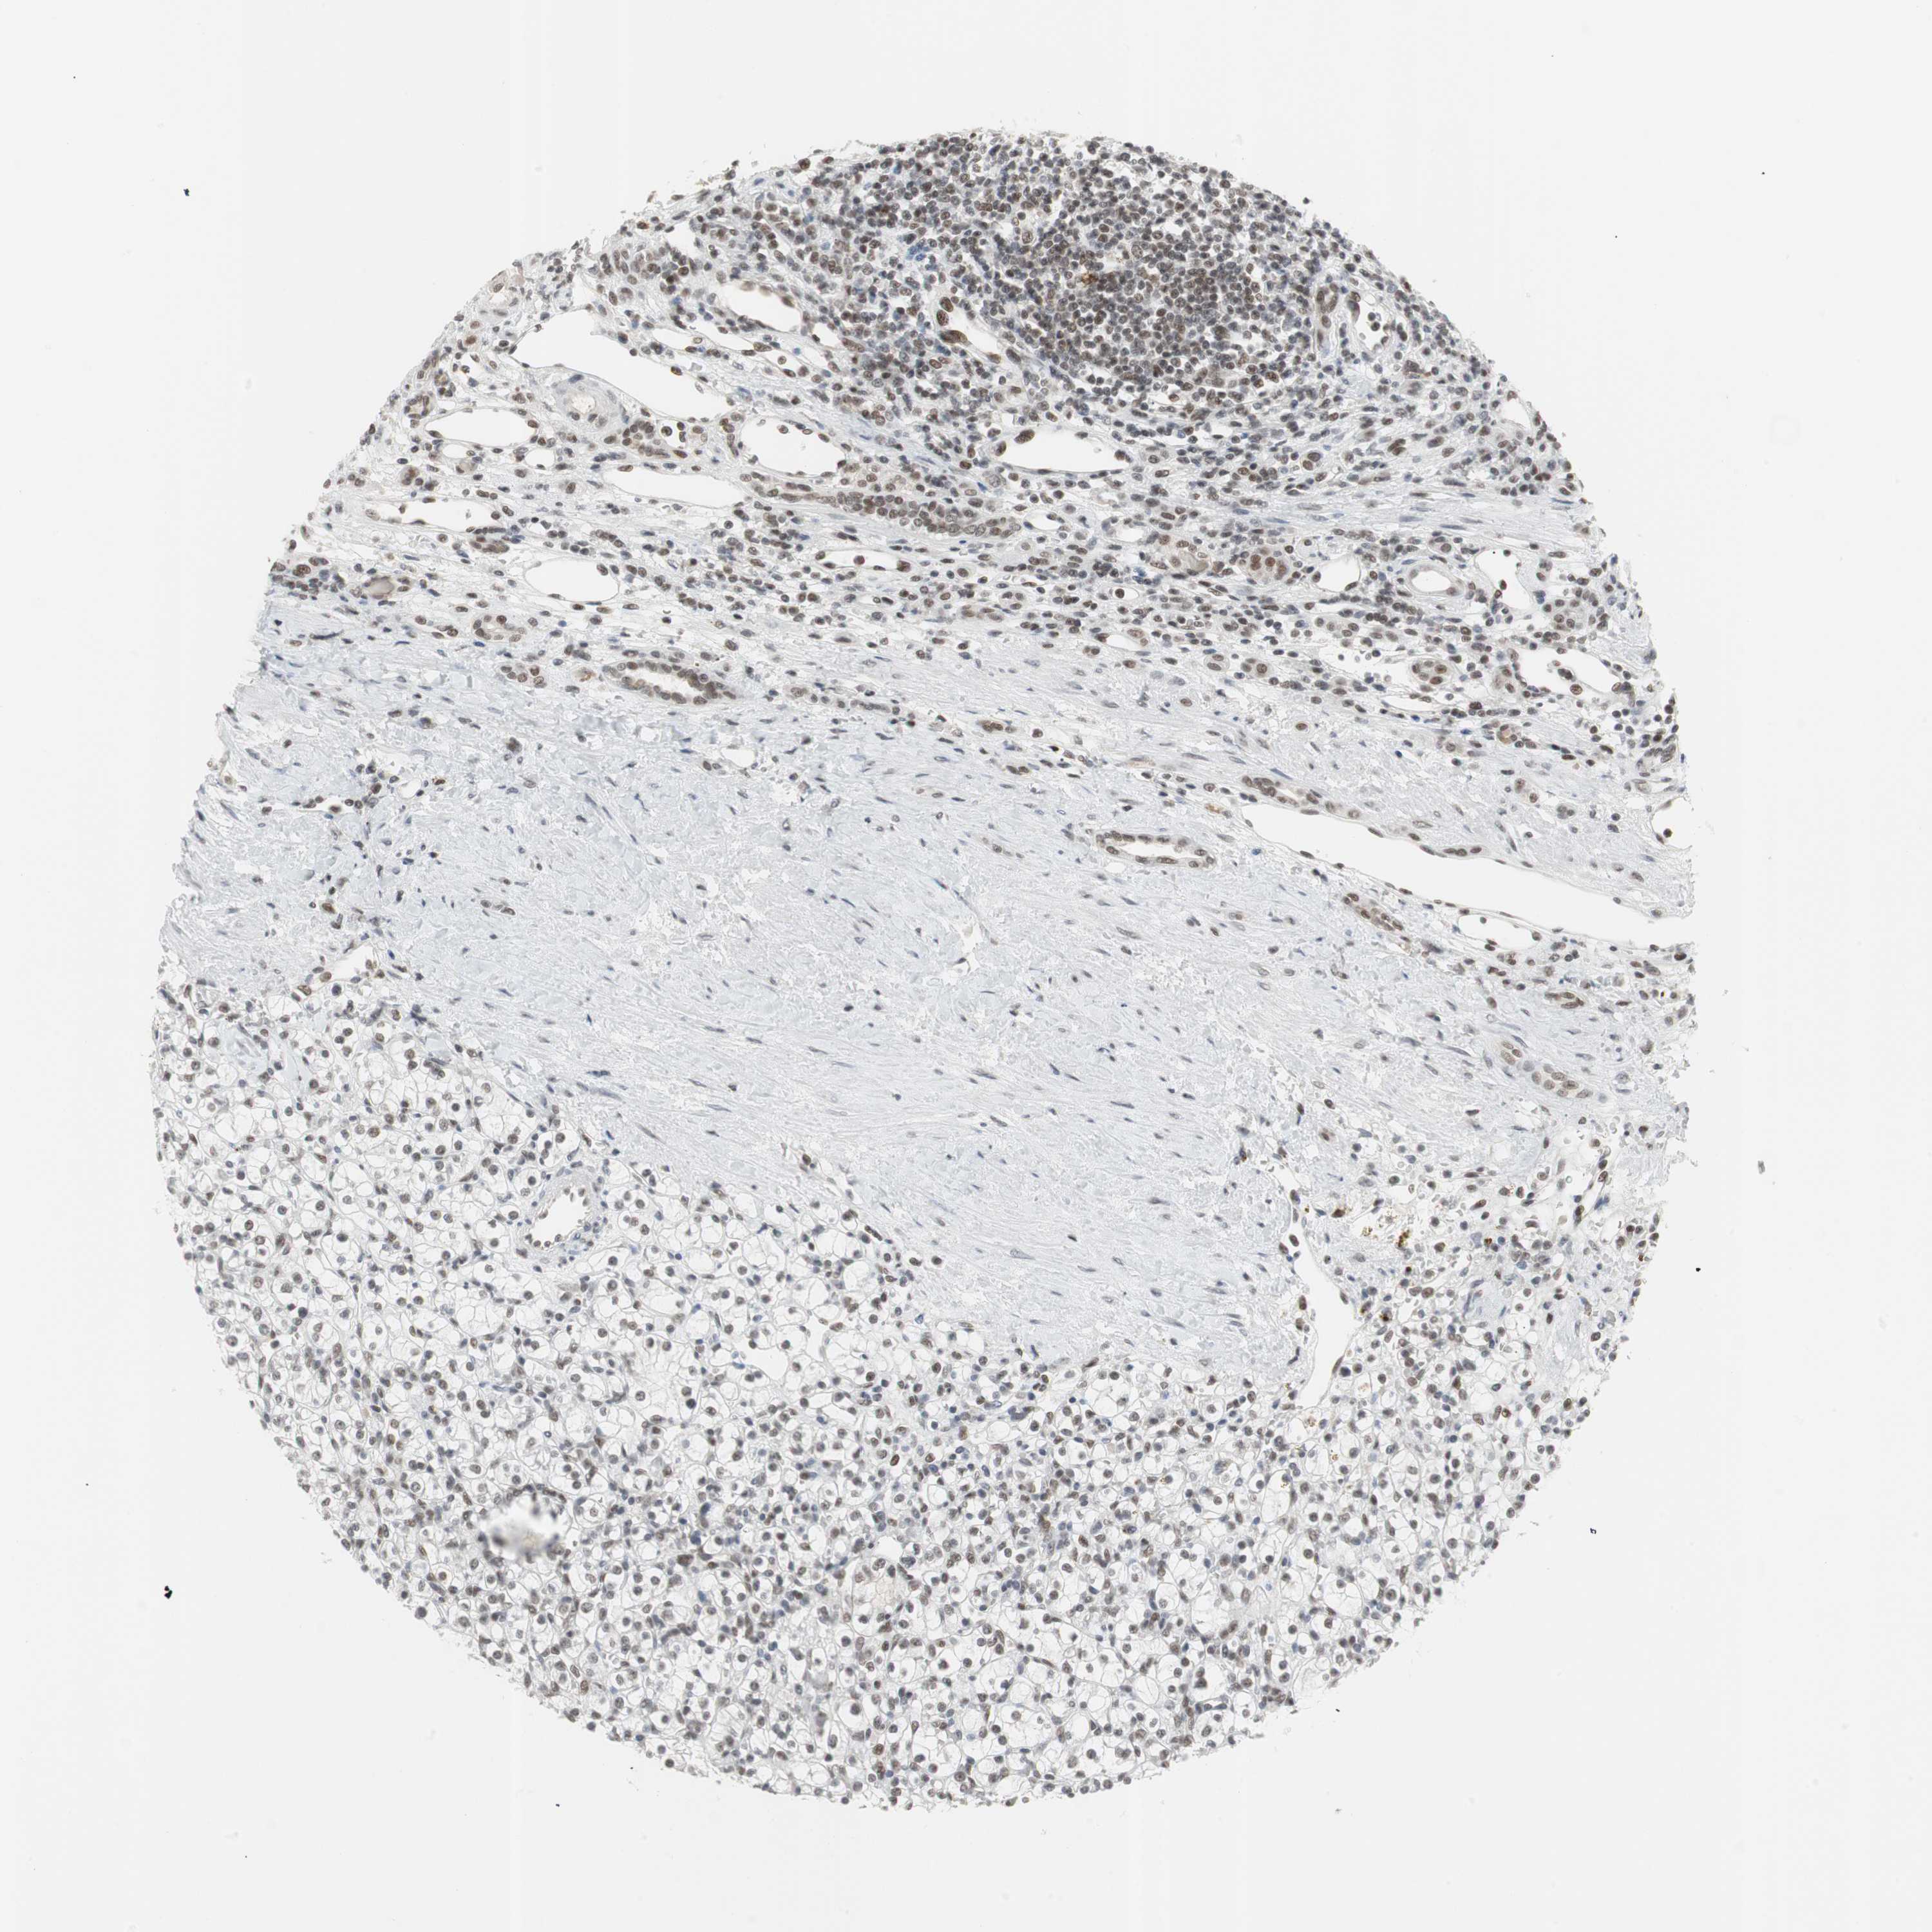

KIDNEY RENAL PAPILLARY CELL CARCINOMA (TCGA) - Interactive survival scatter ploti

The Survival Scatter plot shows the clinical status (i.e. dead or alive) for all individuals in the patient cohort, based on the same data that underlies the corresponding Kaplan-Meier plots. Patients that are alive at last time for follow-up are shown in blue and patients who have died during the study are shown in red.

The x-axis shows the expression levels (FPKM) of the investigated gene in the tumor tissue at the time of diagnosis. The y-axis shows the follow-up time after diagnosis (years). Both axes are complimented with kernel density curves demonstrating the data density over the axes. The top density plot shows the expression levels (FPKM) distribution among dead (red) and alive patients (blue). The right density plot shows the data density of the survived years of dead patients with high and low expression levels respectively, stratified using the cutoff indicated by the vertical dashed line through the Survival Scatter plot. This cutoff is automatically defined based on the FPKM cutoff that minimizes the p-score. The cutoff can be changed by dragging the vertical line or by entering a cutoff value in the square labeled "Current cut-off".

Under the Survival Scatter plot the p-score landscape (black curve; left axis) is shown together with dead median separation (red curve; right axis). Dead median separation is the difference in median mRNA expression between patients who have died with high and low expression, respectively. It is calculated as follows: median FPKM expression of dead patients with high expression - median FPKM expression of dead patients with low expression. This is intended to aid the user in visually exploring custom cutoffs and the associated p-scores and dead median separation.

Individual patient data is displayed and can be filtered by clicking on one or more of the category buttons on the top of the page. Categories describing expression level and patient information include: high, low, alive, dead, female, male and tumor stages. The scale of the x-axis can be toggled between linear and log-scale by clicking on the "x log" button. Mouse-over function shows TCGA ID, patient information and mRNA expression (FPKM) for each patient.

& Survival analysisi

Kaplan-Meier plots summarize results from analysis of correlation between mRNA expression level and patient survival. Patients were divided based on level of expression into one of the two groups "low" (under cut off) or "high" (over cut off). X-axis shows time for survival (years) and y-axis shows the probability of survival, where 1.0 corresponds to 100 percent.

RTF1 is not prognostic in Kidney Renal Papillary Cell Carcinoma (TCGA)

Best expression cut offi

Based on the FPKM value of each gene, patients were classified into two groups and association between prognosis (survival) and gene expression (FPKM) was examined. The best expression cut-off refers the FPKM value that yields maximal difference with regard to survival between the two groups at the lowest log-rank P-value. Best expression cut-off was selected based on survival analysis .

When clicking on this number, the vertical dashed line indicating cut-off, the interactive survival plot, and the Kaplan-Meier curve will be adjusted to show results based on the best expression cut-off.

: 14.12